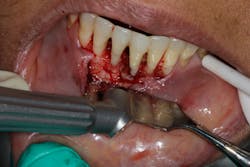

- Proper surgical technique including incision, flap design, and complete detoxification of bony defect and root apices (figures 3 and 3a)

- Appropriate scaffolding material, biologic agent, and/or cell occlusive barrier for periodontal regeneration (figure 4)